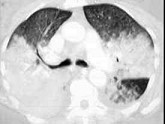

- 单项选择题男,38岁, 咳嗽伴咳白色泡沫痰3周,呼吸困难, CT如图,最可能的诊断是 ( )

A、金葡菌肺炎

B、大叶性肺炎

C、两肺多发段性不张

D、肺泡细胞癌

E、非典型肺炎